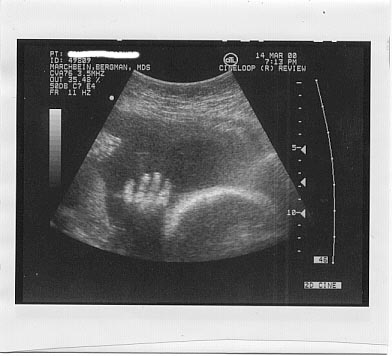

32 weeks 2 days

She is now 5 lbs 1 oz, Not sure how long

Here she is waving! =)